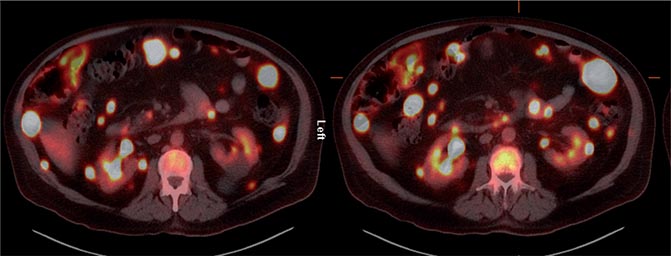

The patient was referred for 18F-FDG-PET/CT the next day to further evaluate the disease extent. A whole-body PET/CT was performed 60 min after the intravenous injection of 629 MBq (17 mCi) 18F-FDG. The study showed multiple hypermetabolic foci throughout the body (Figure 1). There was a large soft tissue mass in the right lower lobe with increased 18F-FDG uptake; the maximum standardized uptake value (SUVmax) of this lesion was 38.0. Also, there were multiple hypermetabolic nodules in the thyroid, gastric mucosa, pancreas, and both the adrenals. Both kidneys contained exophytic lesions with increased 18F-FDG uptake (Figure 2). A circumferential soft tissue mass in the esophagus was hypermetabolic as well. Additional FDG-avid nodules and masses were also found in the peritoneum and omentum; the largest of these had a SUVmax of 68.0. Intense FDG uptake was observed in multiple subcutaneous and intramuscular nodules throughout the body, some of which were thought to represent lymph nodes. Brain magnetic resonance imaging was performed on the same day, which revealed five metastatic lesions measuring up to 1.5 cm in the left frontal lobe, anterior right parietal lobe, and right temporal lobe. At this point, there were multiple candidate lesions for the primary malignancy, such as lung, esophagus, melanoma, or an aggressive lymphoma.

Fig 2

Figure 2. Axial 18F-FDG PET/CT fusion images. Foci of markedly increased 18F-FDG uptake are shown in the peritoneal cavity, and in exophytic lesions in the kidneys bilaterally.

In all three prior reports, 18F-FDG-PET/CT was performed after nephrectomy to evaluate recurrent/metastatic disease and, therefore, evaluation of primary sRCC was not possible. Our patient had metastatic disease of unknown primary origin at the time of the PET/CT study. After the final diagnosis of sRCC, the renal lesions were recognized retrospectively as multiple hypermetabolic exophytic lesions bilaterally, with high 18F-FDG uptake relative to that of normal renal parenchyma. The findings in our patient also demonstrate the high 18F-FDG avidity of sRCC metastatic lesions, consistent with the findings of the three previously reported cases.